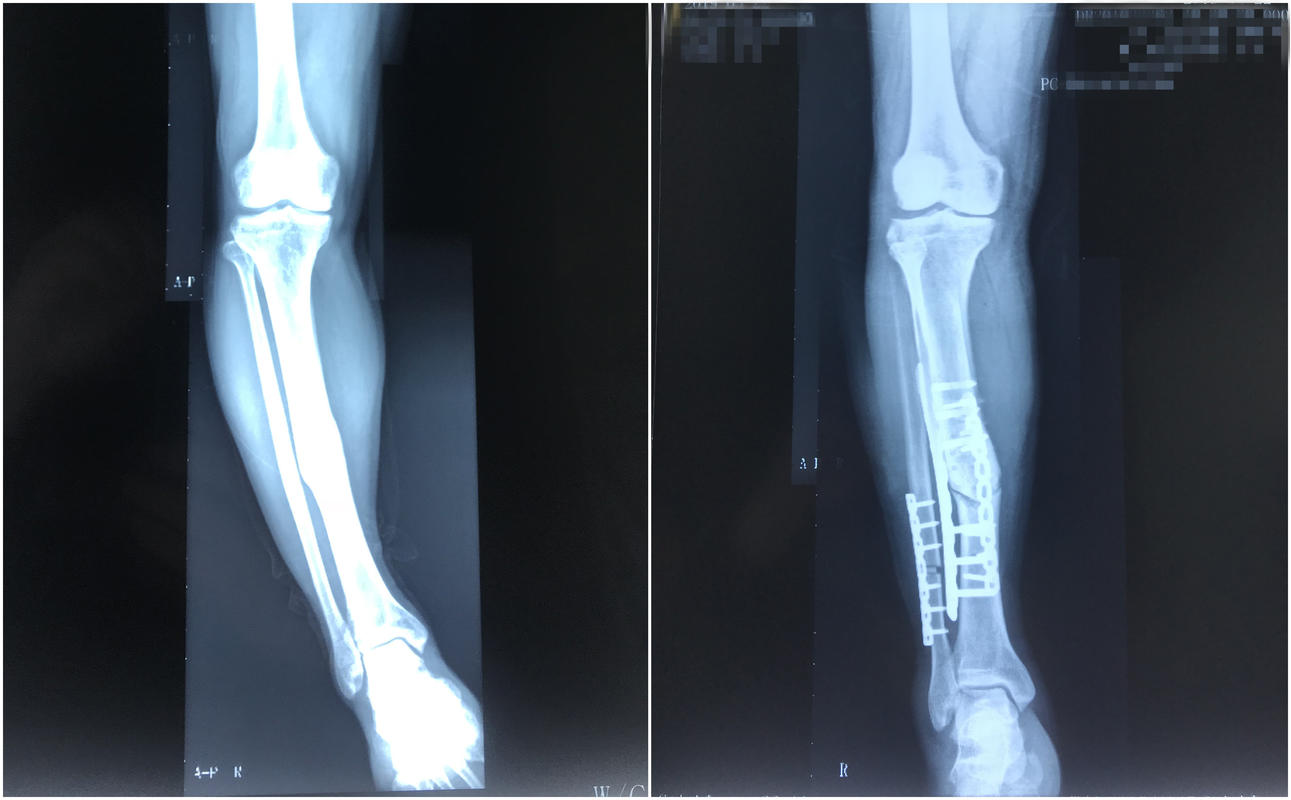

接诊的副主任医师简小飞了解完苏先生的情况,为其进行了细致检查,诊断其为右侧胫骨骨折后畸形,推断其畸形原因可能与其术后过早拆除保护及受力有关,导致恢复不好,骨头“长弯了”。其膝盖的酸痛,是由于下肢力线偏移,长期下来造成了对膝盖的过度受力。3月22日,骨外科专家为苏先生行了下肢力线的重建手术,通过精密测量计算,截骨后将胫骨矫正到正确的力线上,并用钢板进行固定。术后,苏先生的右侧小腿终于不再是“O形”,而是一条直线。目前,苏先生正在平稳恢复中。